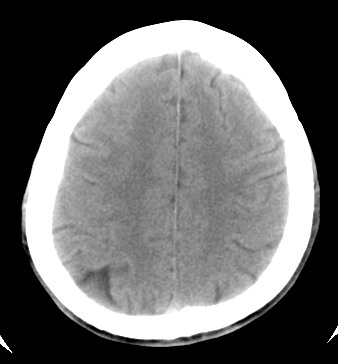

标题: CT17787:头ct,请帮忙看看右顶部有无异常 [打印本页]

标题: CT17787:头ct,请帮忙看看右顶部有无异常

男,58岁,偶有头疼

未见明显异常。右顶部低密度影为深入的脑沟。

增宽的脑沟!无异常!

是宽大的脑沟,局部不象有萎缩现象

增宽的脑沟

诊断依据:

低密度影周围脑组织边缘均有一层脑灰质覆盖。

正常啊,是对右顶增宽脑沟有疑问吗